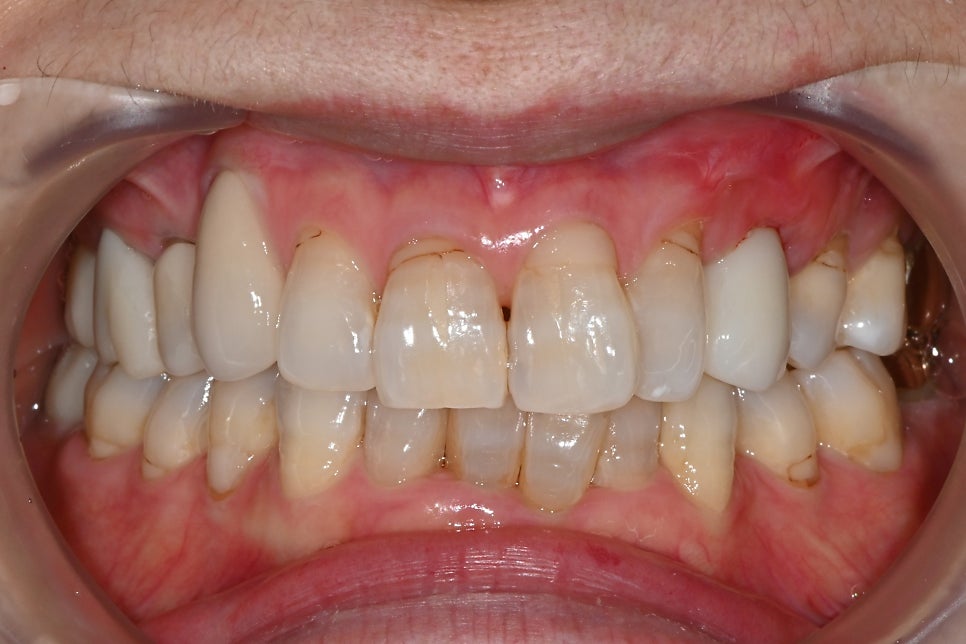

📸 최종 앞니 보철물

앞니 임플란트 완성 정면 사진

환자분 요청대로 살짝 밝은 톤으로 자연스럽게 완성했고,

결과에 매우 만족하셨습니다!